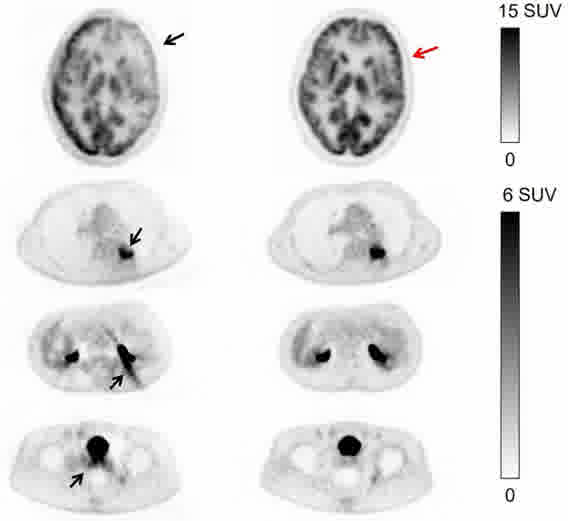

全数据校正

TOF偏差校正

散射校正

基于全链条原始采样数据进行全数字PET信号与图像校正,实现全流程算法智能优化。

CT PET 融合 MIP 无校正 校正后 无校正 校正后 真值图像 传统基于图像的散射校正方法 新型基于能量的散射校正方法 FOV外的高活度射源